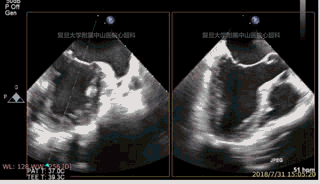

应用X-Plane功能同时显示两个相交切面(如,左室两腔观与左室长轴观),观察穿刺医生手指所在位置,是否在两个切面均位于心尖位置,并判断手指长轴中线延长线是否正对左室长轴观二尖瓣瓣口。心尖穿刺后,即可送入导丝及输送鞘。